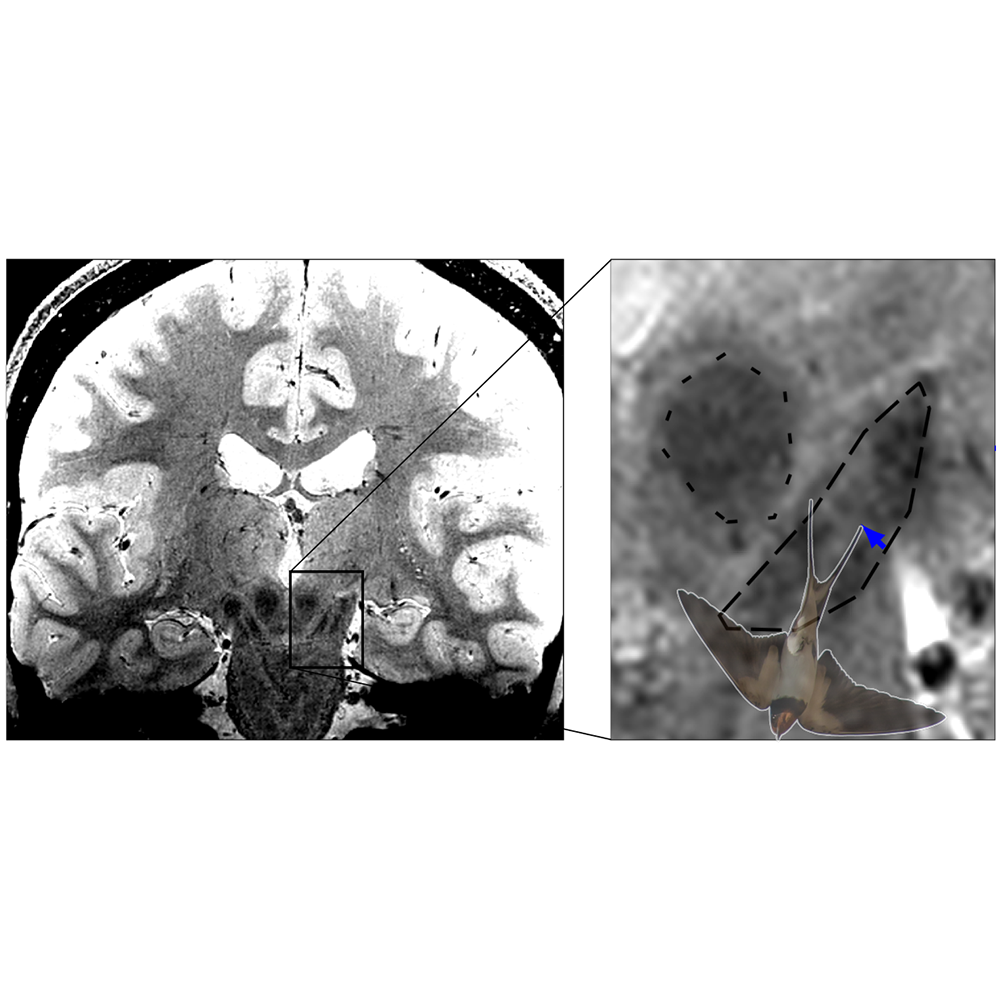

Bei Parkinson sterben dopaminproduzierende Nervenzellen in der Substantia Nigra im Mittelhirn ab, was bei den Betroffenen zu Bewegungsstörungen wie Verlangsamungen, steifen Muskeln und Zittern führt. Besonders stark und früh sind die Nervenzellen im Nigrosom 1 innerhalb der Substantia Nigra betroffen. Mit hochaufgelöster MRT-Bildgebung ist die Abbildung des Schwalbenschwanzzeichens möglich, welches sich im hinteren Drittel der Substantia nigra befindet und nach gängiger Lehrmeinung Nigrosom 1 entspricht. Bei gesunden Menschen erkennt man im MRT-Bild eine signalreiche längliche Struktur, die vorne und an den Seiten von signalarmen Arealen umgeben ist. Diese besondere Form erinnert an einen Schwalbenschwanz, daher spricht man auch vom Schwalbenschwanzzeichen (engl. Swallow tail sign). Nach der gängigen Interpretation des Zeichens führt das Absterben der Neuronen im Nigrosom 1 bei Parkinson-Betroffenen dazu, dass das Schwalbenschwanzzeichen schließlich nicht mehr erkennbar ist. Ist das der Fall, liegt mit hoher Wahrscheinlichkeit eine Parkinson-Erkrankung vor.

Malte Brammerloh und seine Kolleg:innen haben nun mikroskopische 3D-Untersuchungen von menschlichen Gehirnen nach dem Tod mit MRT-Technik kombiniert, um zu zeigen, dass Nigrosom 1 und das radiologische Schwalbenschwanz-Zeichen sich nur teilweise überlappen und in der Tat sehr unterschiedlich sind. Die Wissenschaftler:innen plädieren daher dafür, das Schwalbenschwanz-Zeichen nicht mit der Region Nigrosom 1 gleichzusetzen. Dies erlaubt eine Neuinterpretation des diagnostischen Schwalbenschwanz-Zeichens und eröffnet gleichzeitig neue Wege zur spezifischen Nigrosombildgebung. Brammerloh: „Wir glauben, dass man mit diesem neuen Wissen besser versteht, wie Anatomie und MRT-Kontraste zusammenhängen und wie neue MRT-Marker für die frühe Diagnose von Parkinson entwickelt werden können.“